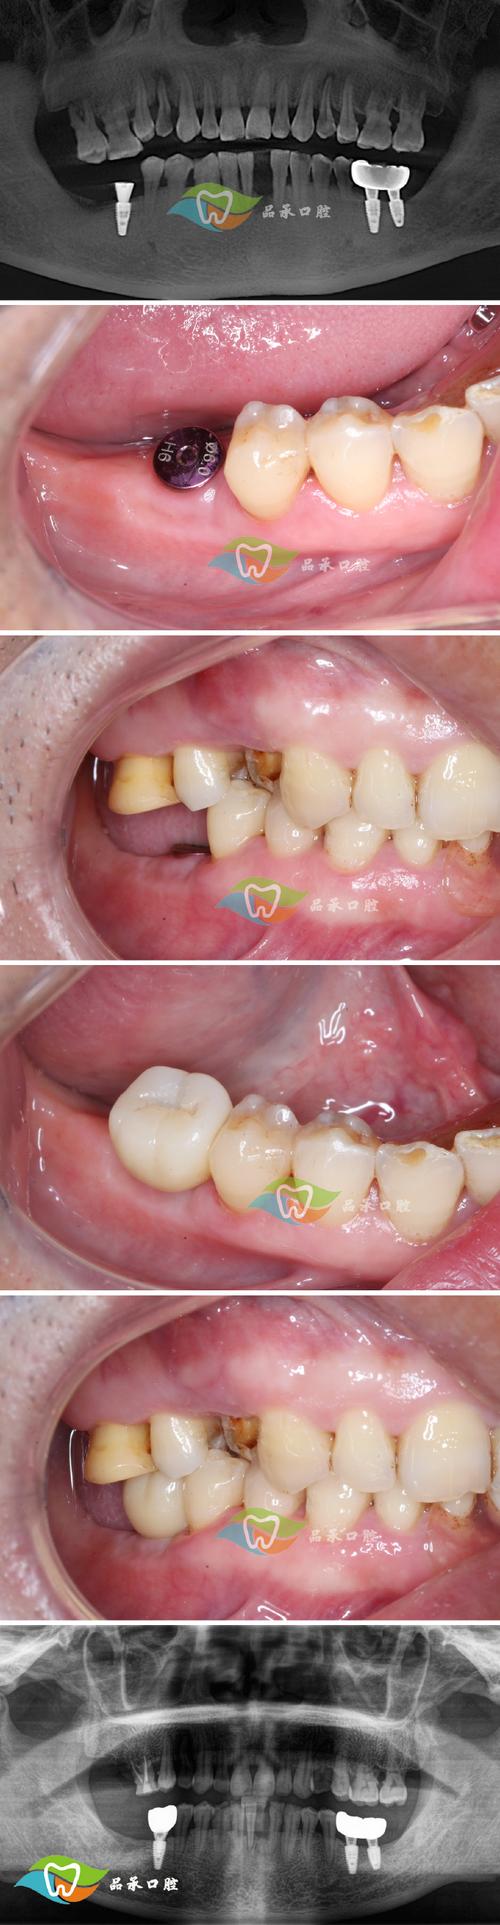

为更直观地理解植牙后牙根晃动的原因及对应表现,可参考下表:

| 常见原因 | 典型表现 | 处理原则 |

|---|---|---|

| 种植体周围炎 | 牙龈红肿、出血、溢脓,种植体轻微松动,可能伴随口臭 | 立即就医,进行种植体周围刮治、抗菌治疗,控制炎症 |

| 骨结合失败 | 种植体明显松动,无疼痛(早期)或伴疼痛(晚期),X线显示种植体周围透射影 | 根据松动程度,可能需取出种植体,待骨愈合后重新植入 |

| 咬合异常 | 咀嚼时种植体区疼痛,牙冠有高点,松动随咬合使用加重 | 调整咬合,降低牙冠高点,必要时重新制作修复体 |

| 外力撞击或过早负重 | 明确外伤史或过早啃硬物后出现松动,可能伴牙龈肿胀 | 避免使用患侧,及时复查,评估种植体稳定性,必要时固定 |